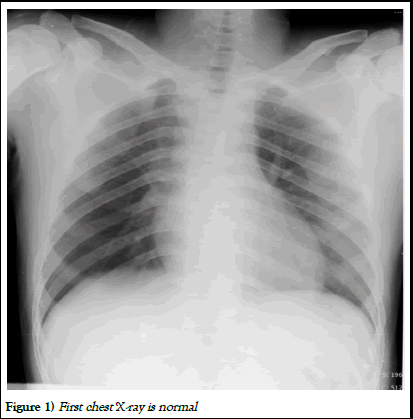

At presentation pulse rate 110 bpm, blood pressure 130/70 mmHg, SpO2 96% on room air, respiratory rate 18 cycles/minute, GRBS 150 mg/dl. General physical examination and systemic examination was normal. Admission chest X-ray was normal. ECG showed sinus tachycardia. Lab investigations sent for CBC, RFT, LFT, serum electrolytes and serology for HIV and hepatitis B was normal [3].

Figure 1) First chest X-ray is normal